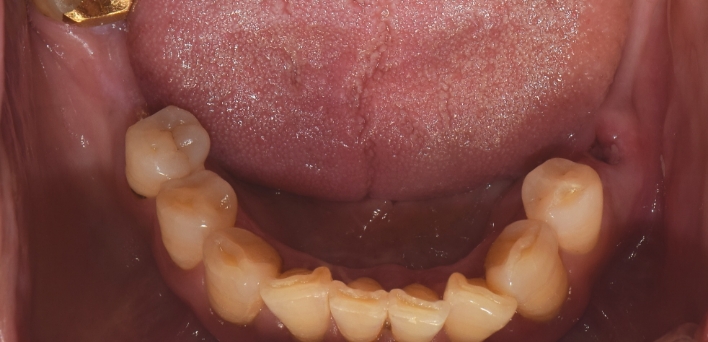

임플란트 : 손 ** 님 (50대)

치아가 있다는게, 아직도 정말 꿈만 같아요.

Before Before

2020.02.30

After After

※ 더서울치과의원은 의료법을 준수하며 위 케이스는 실제 환자의 동의를 얻은 사례로 치료 전, 후가 동일한 환경에서 촬영되었습니다.

환자 케이스에 따라 부작용이 발생할 수 있습니다. 이 부분은 의료진의 충분한 상담과 체크를 통해 예방하고 줄일 수 있습니다.

[임플란트 부작용] 수술 후 관리가 소홀할 경우 출혈, 주위염 등의 부작용이 발생할 수 있어 구강 위생을 철저히 유지하고, 정기적인 검진을 통해 상태를 점검하는 것이 중요합니다.

환자 특징

환자 특징01무치악 상태

환자 특징02수년간 무치악으로 지내심

임플란트가 불가능할것이라

생각하고 내원

위, 아래 6개씩 식립

디지털 풀아치 임플란트

임플란트 Before & After